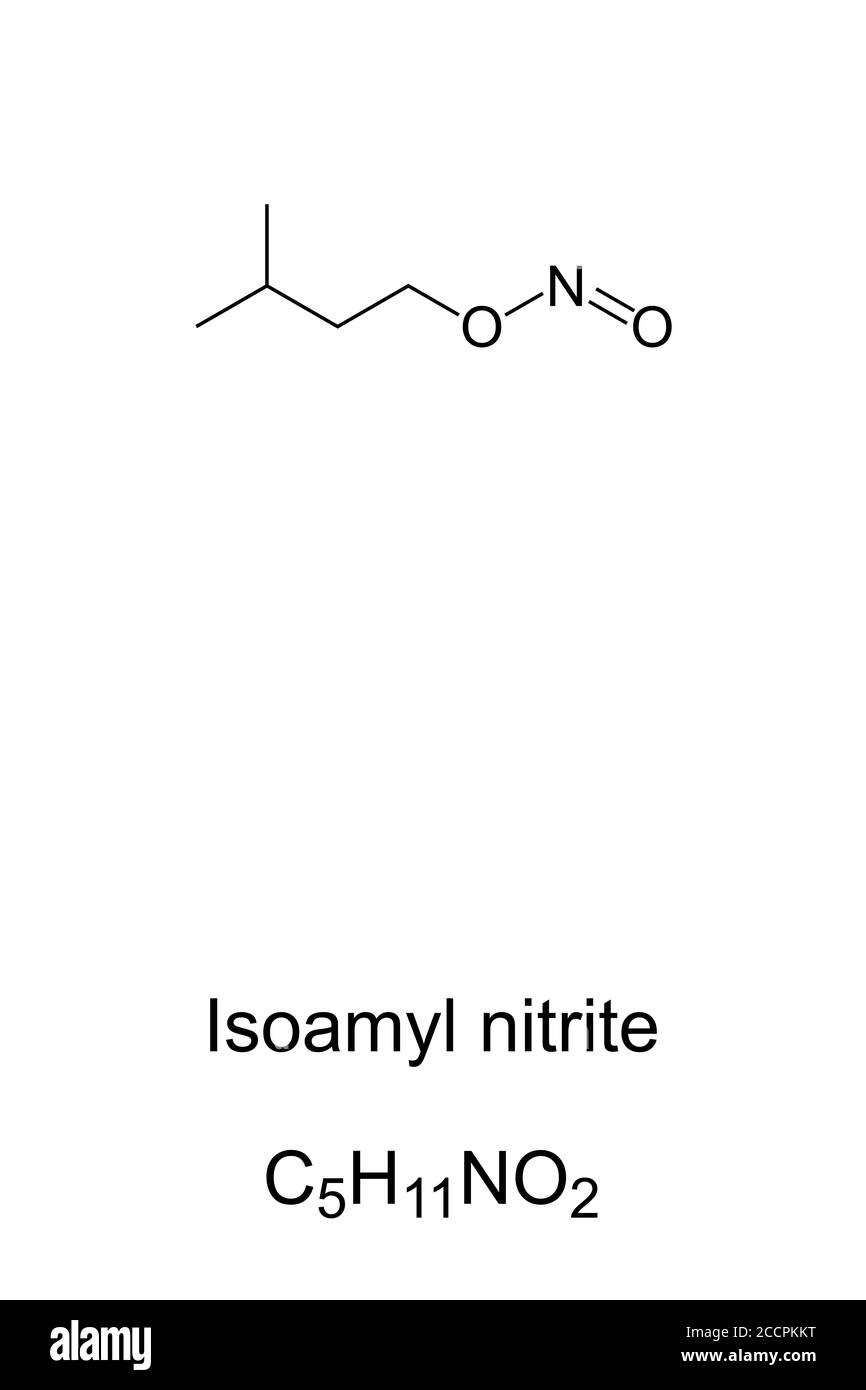

RF2CCPKKT–Nitrito di isoamile, nitrito di amile, noto come poppers, struttura chimica. Come inalante è una droga ricreativa con effetti psicoattivi. Un vasodilatatore.